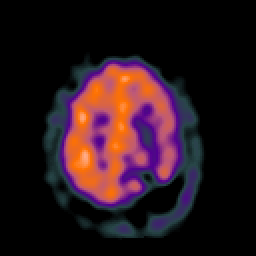

SPECT TC Study #2 -- Slice #40

[Home][Help][Clinical][Tour 1][Tour 2][Tour 3] Slice 40